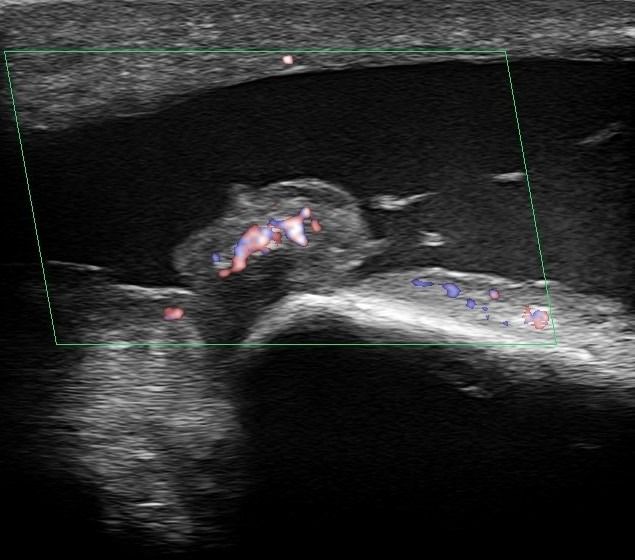

- Fluid collection in the bursa (i.e olecranon bursitis)

- Synovitis in the bursa as a symptom of Rheumatologic Disease